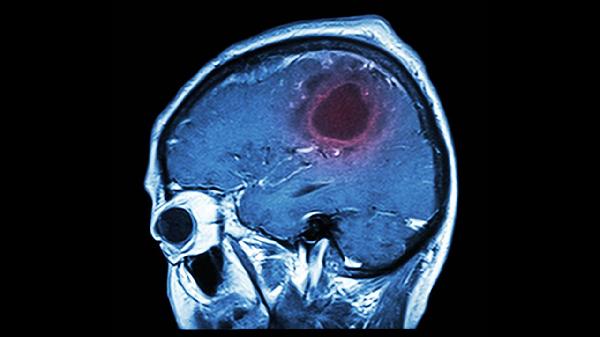

颅骨修补手术是为了修复因外伤、疾病或手术导致的颅骨缺损,恢复头部外观和保护脑组织。手术本身技术成熟,但术后仍可能出现一些并发症或后遗症。